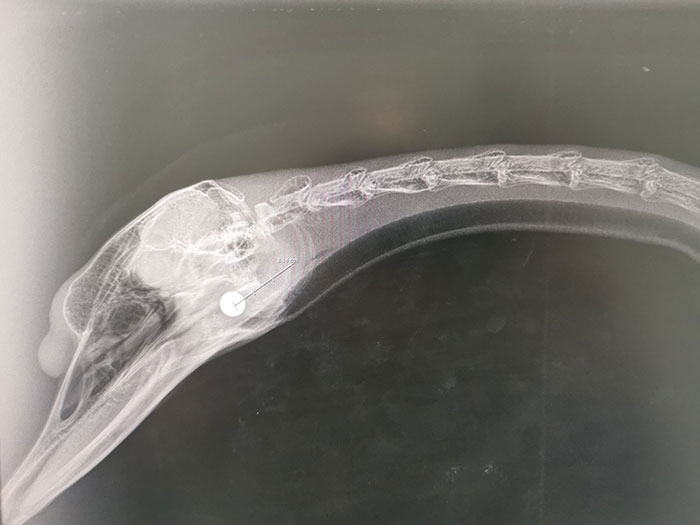

Recently, the police started an investigation when 5 swans were shot with an air rifle. One of them was shot in the head while tending to her unhatched eggs.

The vets had to remove an 8mm ball fired from an air weapon.